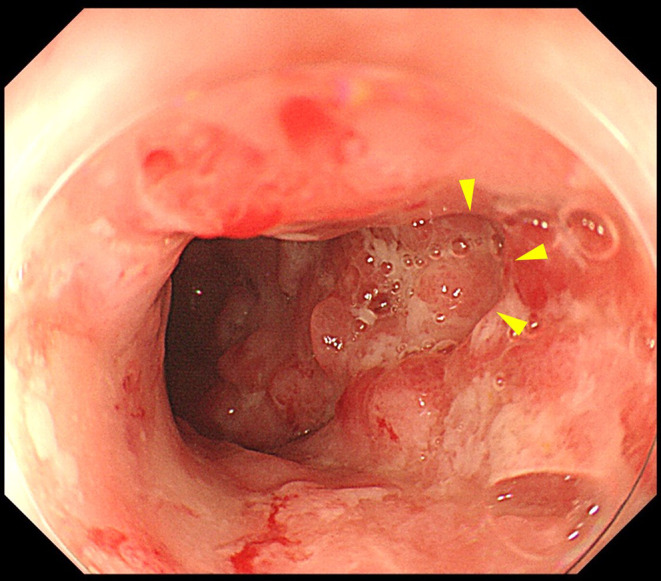

患者是一名 50 岁的日本女性,26 岁时被诊断出患有全结肠炎型溃疡性结肠炎(UC)。她接受了美沙拉嗪和硫唑嘌呤治疗,疾病活动得到了很好的控制。50 岁时,患者出现发热、腹痛、腹泻、血便和肛门疼痛,因此被诊断为 UC 复发。虽然进行了类固醇治疗,症状有所改善,但还是出现了粪便样阴道分泌物,并确诊为直肠阴道瘘(RVF)。患者接受了结肠造口术,并开始使用英夫利西单抗作为 UC 的维持治疗。所有症状均有所改善,在开始使用英夫利昔单抗 6 个月后,确认直肠阴道瘘闭合。迄今为止,她的 UC 一直没有复发。目前只有少数 UC 并发 RVF 的报道,而且这种情况通常很难治疗。据我们所知,此前还没有其他病例在接受结肠造口术和英夫利昔单抗治疗后瘘管闭合的病例;因此,我们对本例病例的报告在文献中具有重要价值。

The patient was a 50-year-old Japanese woman who was diagnosed with total-colitis-type ulcerative colitis (UC) at the age of 26 years. She was treated with mesalazine and azathioprine, and her disease activity was well controlled. At the age of 50 years, the patient was experiencing fever, abdominal pain, diarrhea, bloody stool, and anal pain, which led to a diagnosis of a relapse of UC. Although steroid therapy was administered and tended to improve her symptoms, fecaloid vaginal discharge occurred, and rectovaginal fistula (RVF) was confirmed. Colostomy was performed, and infliximab was initiated as maintenance therapy for UC. All symptoms improved, and RVF closure was confirmed 6 months after the initiation of infliximab. To date, she has been free from relapse of UC. There have been only a few reports of UC complicated by RVF, and this condition is often difficult to treat. To the best of our knowledge, no other case of UC complicated by RVF in which the fistula was closed after treatment with colostomy and infliximab has been previously reported; thus, our report of the present case is valuable to the literature.